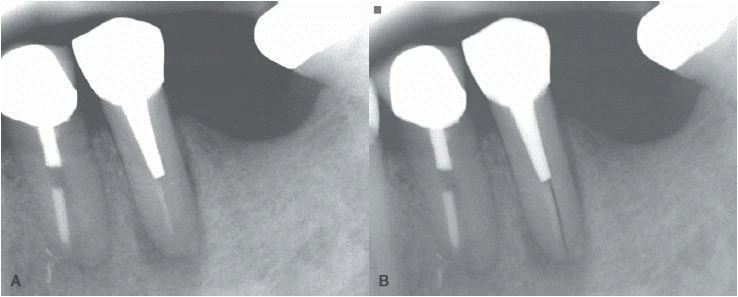

- Ống tuỷ rộng hơn bình thường so với ống tuỷ của chân răng cạnh đó

- Vùng thấu quang xuất hiện giữa trục chính của vật liệu trám bít ống tuỷ (hoặc chốt) và thành ống tuỷ.

- Vùng mất xương ở phía gần và xa chân răng. Khi nứt dọc chân răng hoặc chia chân răng mở rộng từ phía gần đến phía xa của răng thì thường toàn bộ dây chằng nha chu quanh răng sẽ giãn rộng không điển hình.

Hình 15. Khi răng có ống tuỷ rộng hơn so với răng cùng loại hoặc so với răng cạnh nó thì nên nghi ngờ có nứt dọc chân răng

Hình 16. Khi có khoảng trống giữa chất trám bít ống tuỷ và thành ống tuỷ thì nghi ngờ cao có chia chân răng.